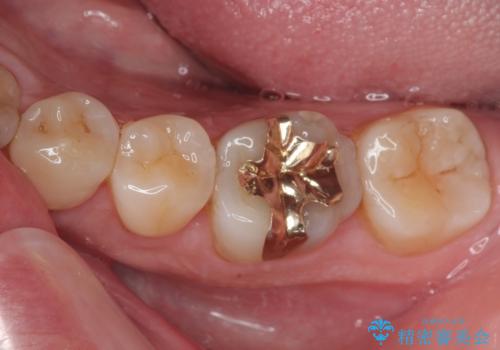

「他の歯も、せっかくなら精度の良いものに替えておきたい」とのご希望があり、

上顎左側第一大臼歯

下顎左側第一大臼歯

に入っていた保険診療の銀歯(メタルインレー)を、精度の良いゴールドインレーへやり替えを行いました。

詰め物や被せ物は、精度が低いと隙間から虫歯(=二次う蝕)になりやすいという問題があります。

精度の高い補綴物を選ぶことで、将来的な治療回数を減らし、歯を長く守ることが可能です。